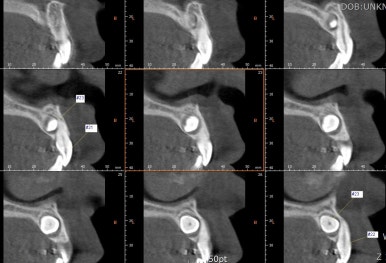

부산매복치아교정 키다리아저씨치과에서 촬영한 3D CT에서는 이처럼 입체를 연속적인 단면으로 재구성하여 정확한 위치를 파악할 수 있게 해줍니다.

매복치의 위치는 가로로 누워있고, 머리는 앞쪽, 뿌리는 뒤쪽을 향하며 다른 치아들보다 입천장쪽에 있습니다.